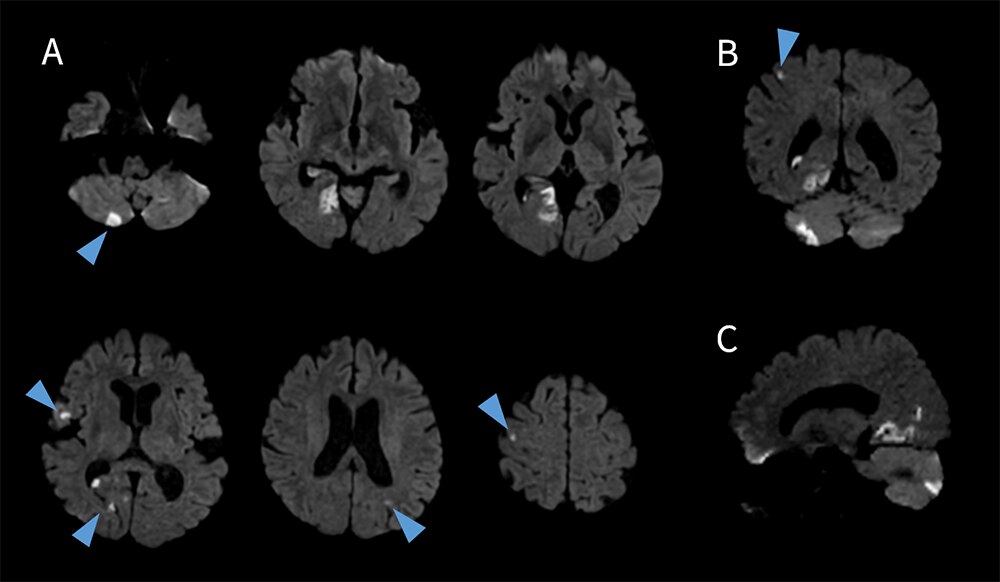

頭部領域での臨床応用 ~脳梗塞患者へVolume DWIの追加~

当院にはウォークインで来院され、症状も数日前の頭痛・めまい・ふらつきなどの主訴の患者が多く、主血管閉塞による脳梗塞よりも微小脳梗塞を疑う症例が多い。当院では、脳梗塞疑いの患者においては、Volume DWIを追加している(図6)。

図6 脳梗塞患者におけるVolume DWI

A. Volume DWI Axial、B. Coronal Reformat、C. Sagittal Reformat

スライス厚:2.2mm 撮像時間:2:40 min

Volume DWI は通常のDWI(Conventional DWI)よりもスライス厚が薄いため、微小脳梗塞の検出に優れ、MPR処理することにより他方向からの観察も容易となる一方で、SNRが低下しやすいデメリットがある。従来はSNRを担保するためには加算回数を増やす必要があり、予約時間枠外での撮像を余儀なくされていたが、AIR™ Recon DLによってConventional DWIと遜色ないSNRのVolume DWIを3分以内で撮像することが可能となり、予約検査時間内での追加撮像を可能としている。